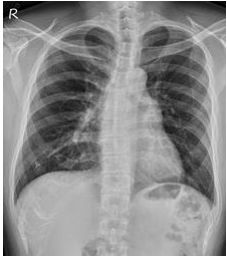

1. A 39-year-old man had this chest X-ray on his health exam. No any clinical symptoms.